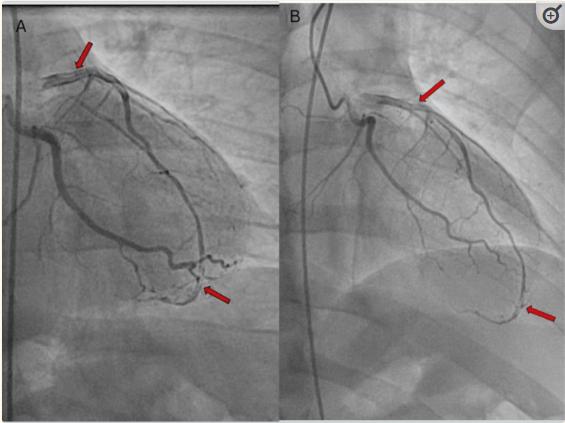

随后,患者接受了诊断性导管插入术,显示左侧优势循环。发现患者左前降支动脉出现1型自发性冠状动脉夹层,从近端开始,延伸至整个动脉,心肌梗死溶栓(TIMI)流程3(图2)。所有其他血管被发现完全开放。支架植入被认为风险太大,因为有可能加剧夹层,导致决定对患者进行保守治疗。患者接受了阿司匹林、氯吡格雷、阿托伐他汀和酒石酸美托洛尔的药物治疗。实现了有效的控制疾病的心率和血压,并建议患者限制体力活动,避免重物提起。出院时,患者病情稳定,症状明显改善。此外,患者被转介到心脏康复计划,并安排了密切的门诊随访。

图2、左前降支(LAD)近端段的1型自发性冠状动脉夹层,涉及整个LAD,TIMI血流3 (A和B)。箭头指向多个射线可透过的管腔。TIMI:心肌梗死的溶栓治疗